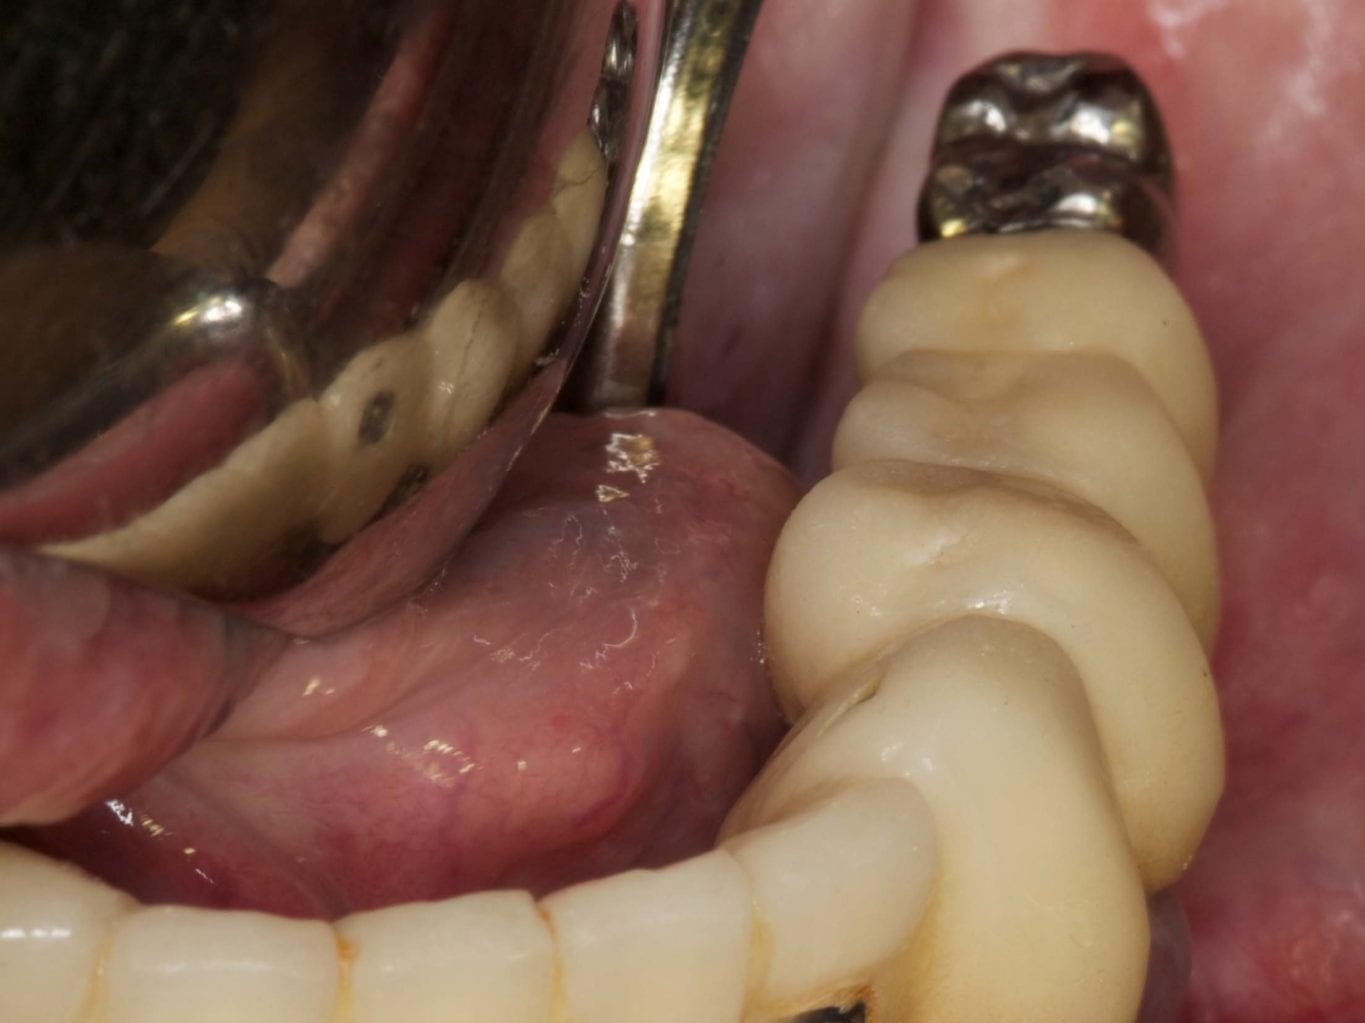

Für die Allgemeinanästhesie erfolgte zunächst die zusätzliche Gabe eines typischen Infiltrationsanästhetikums. Intravenös wurde unmittelbar präoperativ das Antibiotikum Clindamycin 600 mg gegeben. Abbildung 7 zeigt die klinische Ausgangssituation linksseitig. Nach der vorsichtigen Durchtrennung der Brückenkonstruktion (Abb. 8) jeweils vor der Krone auf den Blattimplantaten und Entfernung der nicht erhaltungswürdigen Zähne 44 bis 33 samt ihrer Überkronung (Abb. 9) wurde der Mukoperiostlappen vestibulär wie lingual passend zur erstellten Schablone präpariert und die Bohrschablone in ihrer finalen Lage eingebracht (Abb. 10). Zunächst erfolgte die Insertion der angulierten Implantate Ankylos ® C/X-Implantate (Durchmesser 3,5 mm) der Länge 14 mm in regio 034 (Abb. 11 und 12) und 044. Danach wurden in den Positionen 032 und 042 jeweils ein weiteres Ankylos ® C/X –A-Implantat mit gleicher Länge und Durchmesser inseriert (Abb. 13). Sämtliche entfernten Knochenpartikel und auch Bohrspäne wurden akribisch asserviert. In den Positionen 032 und 042 wurden Ankylos ® Balance Basisaufbauten C/ (GH 3,0 / Ø 5,5 mm, Kopfhöhe 2,4 mm) mit 15 N/cm eingeschraubt. Anschließend hat der Zahntechniker mittels der Ankylos ® Modellierhilfskappenfür den Balance Basisaufbau Retentionskappen hergestellt, die mit 25 N/cm eingebracht wurden (Abb. 14). Am Implantat regio 042 wurde der Knochen in Schalentechnik nach vestibulär aufgebaut (Abb. 15)⁹,¹⁰. Im nächsten Schritt haben wir die angulierten Ankylos ® Balance Basisaufbauten C (nicht indexierte Abutments) in Regio 034 und 044 (GH 3,0, A30 / Ø 4,2 mm, Kopfhöhe 1,3 mm) ausgerichtet und ihren spezifischen Vorgaben entsprechend eingebracht (Abb. 16). Nachdem sich alle erforderlichen prothetischen Implantatbauteile in situ befanden (Abb. 17), erfolgte die Überprüfung und geringfügige Anpassung des im Vorfeld digital erstellten Sofortprovisoriums. Im Anschluss wurden die leeren Alveolen und Knochendefekte mit dem gewonnenen autologen partikulären Material aufgefüllt. Dann erfolgte der typische Naht-Wund-Verschluss mit Einzelknopfnähten eines resorbierbaren Nahtmaterials (Abb. 18). Nachdem die Patientin aus der Vollnarkose erwacht war und ihre motorischen Fähigkeiten wiedererlangt hatte, wurde das Sofortprovisorium eingesetzt und in Okklusion gebracht. In dieser Position wurden die Retentionskappen über ein selbsthärtendes fluoreszierendes kaltpolymerisierendes Paste-Kartuschensystem fixiert. Anschließend erfolgte die extraorale Versäuberung des Interimszahnersatzes. Nach Refixierung des Sofortprovisoriums in der Mundhöhle (Abb. 19 und 20) und dem Verschluss der Schraubenkanäle mit Kunststoff erfolgte die radiologische Kontrolluntersuchung (Abb. 21).